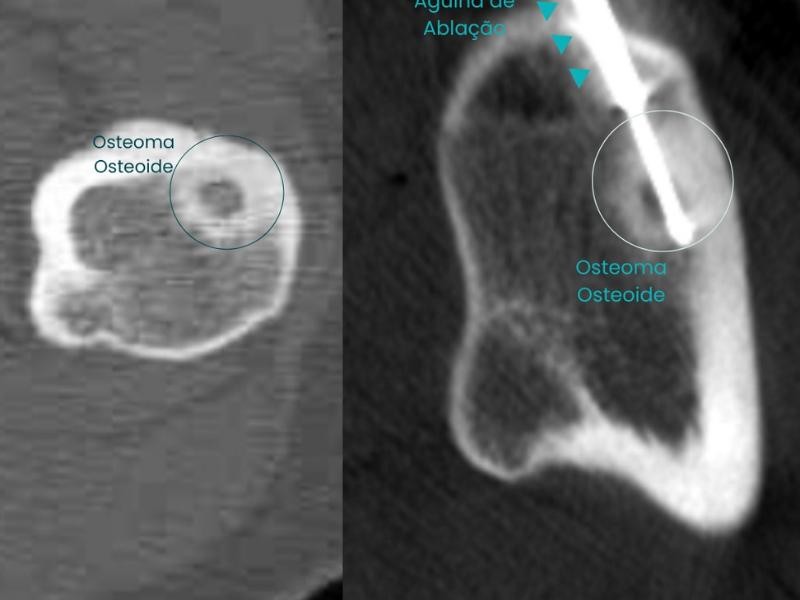

Primeiramente o paciente recebe pomada anestésica e anestesia local para evitar qualquer incomodo. O procedimento é realizado com auxílio de ultrassom ou tomografia para guiar a introdução de uma agulha dentro do cisto. O líquido é aspirado, e em seguida, um agente esclerosante, como álcool absoluto e polidocanol, é injetado para obliterar a cavidade e impedir sua recidiva.